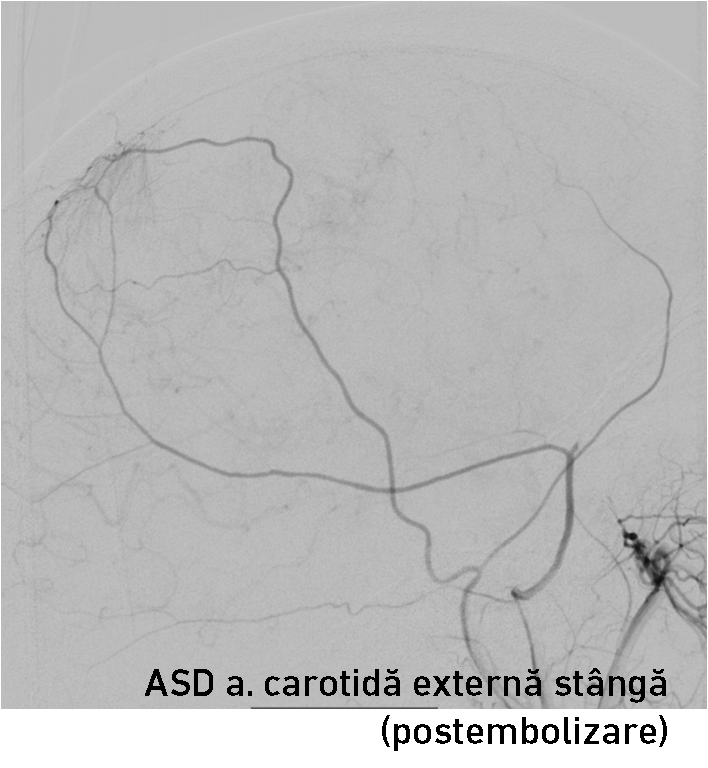

Tratamentul  endovascular al unei tumorii constă în introducerea agenților embolici înpediculii arteriali ce alimentează tumora până la ocluzia lor. Embolizarea tumorii poate fi realizată nemijlocit înaintea intervenției sau câteva zile în prealabil. Ocluzia arterelor ce alimentează tumora determină apariția leziunilor ischemice intratumorale (necroză centro-tumorală) și la nivelul atașamentului dural al meningiomului. În cazul dat am optat pentru embolizarea AMM stângi cu particule emboligene de 150-250 mcm care avansează intratumoral și în final realizează ocluzia mecanică al arterei feeder. A fost realizat cateterismul supraselectiv al AMM cu un microcateter (fig. 5-6) și prin el s-au injectat agenții embolici. Angiografia selectivă a arterei carotide externe stângi a confirmat diminuarea semnificativă al blush-ului tumoral și ocluzia AMM stângi (fig. 7).

endovascular al unei tumorii constă în introducerea agenților embolici înpediculii arteriali ce alimentează tumora până la ocluzia lor. Embolizarea tumorii poate fi realizată nemijlocit înaintea intervenției sau câteva zile în prealabil. Ocluzia arterelor ce alimentează tumora determină apariția leziunilor ischemice intratumorale (necroză centro-tumorală) și la nivelul atașamentului dural al meningiomului. În cazul dat am optat pentru embolizarea AMM stângi cu particule emboligene de 150-250 mcm care avansează intratumoral și în final realizează ocluzia mecanică al arterei feeder. A fost realizat cateterismul supraselectiv al AMM cu un microcateter (fig. 5-6) și prin el s-au injectat agenții embolici. Angiografia selectivă a arterei carotide externe stângi a confirmat diminuarea semnificativă al blush-ului tumoral și ocluzia AMM stângi (fig. 7).